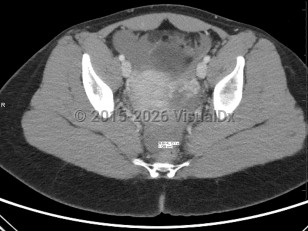

The term ectopic pregnancy refers to implantation of a developing blastocyst at any location outside of the endometrial cavity. Ectopic pregnancies can be found in the cervix, cornua, fallopian tubes, ovaries, or a prior cesarean delivery scar, or, more rarely, attached to the abdominal lining, bowel, or other viscera. The most common location is the fallopian tube, specifically the ampulla, which accounts for about 70%-80% of cases, followed by the isthmus and fimbria. Prevalence is estimated at 25 in 1000 pregnancies, with fewer than 200 000 cases in the United States per year. It is a medical emergency.

Presentation can vary. Patients may present with a positive home pregnancy test and unilateral lower quadrant pain that is often sharp / stabbing in nature. Some will present after tubal rupture and be hemodynamically unstable. Others may present with only vaginal spotting and be unaware they are even pregnant. Therefore, one must have a high index of suspicion when a patient arrives with a positive pregnancy test and symptomatology. As many as 18% of women presenting to the emergency department with first-trimester bleeding, pain, or both will be found to have an ectopic pregnancy.